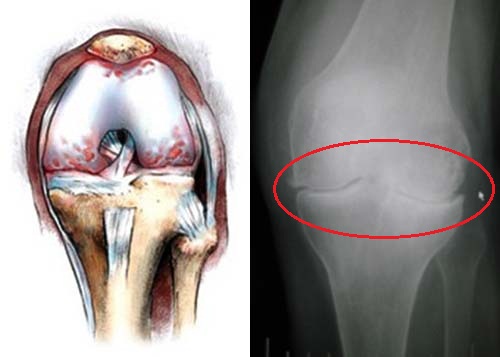

разрыв менисков (рис 4);

Рис.4 - нестабильность колена;

- «суставные мыши» — осколки хряща или кости, находящиеся в суставной полости;

- болезнь Кенига, или отсекающий остеохондрит;

При гонартрозе деформируются кости, разрушаются суставный хрящ и внутрисуставные структуры, воспаляется синовиальная оболочка. Обычно болезнь лечат консервативно, но иногда (при разрыве мениска, «костных разрастаниях», «суставных мышах») возникает необходимость в операции (рис 11).